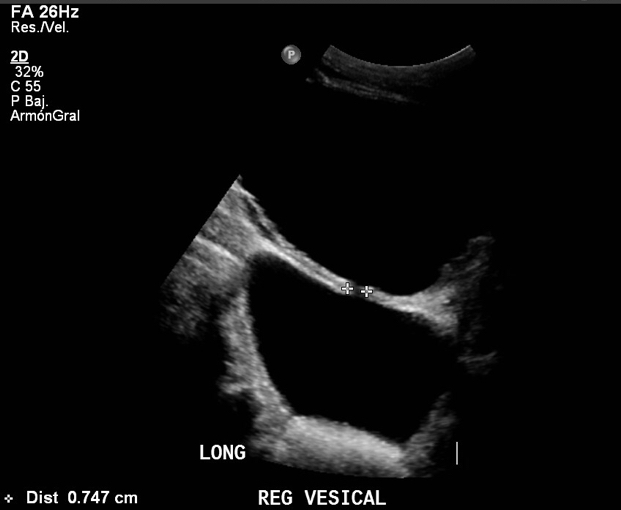

Leve irregularidad de bordes vesicales. En su lumen, se observan múltiples pequeños cálculos móviles a los cambios de posición, que no obstruyen unión ureterovesical distal. Se observa además gran divertículo vesical con cuello que demuestra flujo urinario bidireccional, en donde también se observan múltiples pequeños cálculos móviles a los cambios de posición.

*Se mide pre y post micción a nivel de vejiga, vejiga + diverticulo y diverticulo.